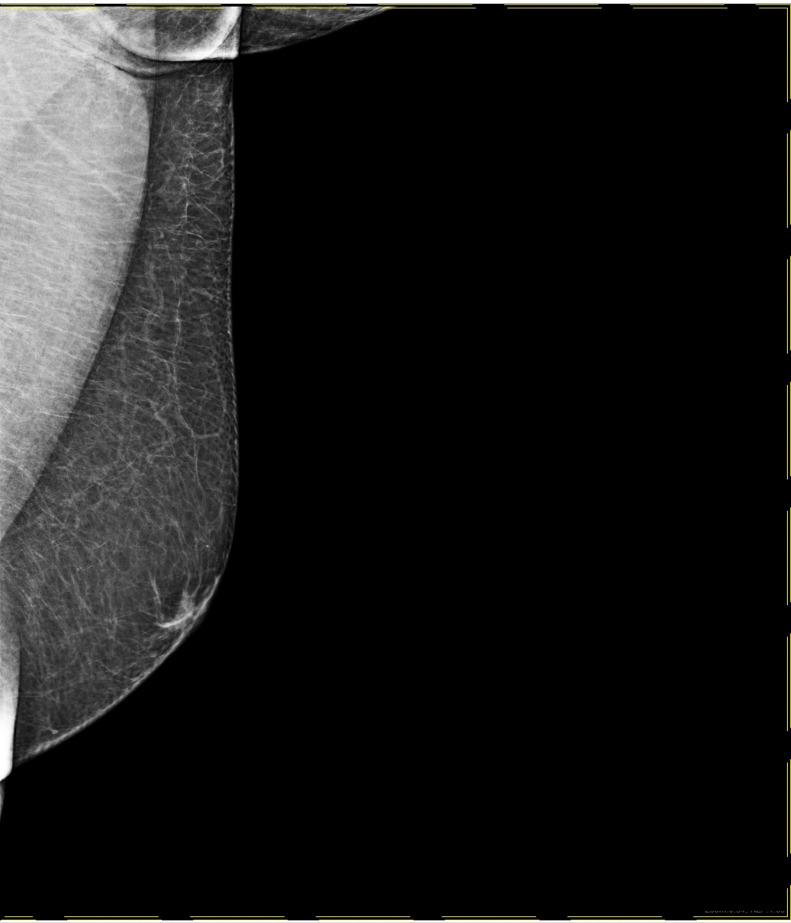

Breast abscess in males is a rare condition, which accounts for 1%-3% of all documented breast diseases. Males with certain risk factors may develop a breast abscess. The ultrasonographic, mammographic, and pathological characteristics of this case will be highlighted in the report. A 51-year-old morbidly obese Saudi male who is a 160-pack-years smoker presented to our surgical clinic complaining of a right breast mass that presented a long time ago and was changing in size. The mass was painless until 5 days prior to presentation. On physical examination, a firm nonmobile 3 × 4 cm mass was felt at 10-12-o'clock, 1 cm away from the nipple. A bilateral X-ray mammogram and ultrasound were performed with fine needle aspiration and culture. The mammogram of the right breast showed a well-circumscribed subareolar mass with equal density, and it was also associated with overlying skin thickening and relative breast parenchymal edema. The fine needle aspiration grossly showed yellowish-green turbid content followed by turbid blood. The anaerobic culture results showed the gram-positive cocci, Finegoldia Magna. The patient was then instructed to take an antibiotic accordingly and return after 1 week. Fine needle aspiration and culture were performed again after antibiotics and grossly showed 2-3 cc of pus without any growth in culture. Male breast disorders are typically benign, with gynecomastia being the most prevalent, and malignancy being the most serious despite its rarity. Breast abscesses are a challenging clinical condition, and radiologists have a pivotal role in evaluation and follow-up of these lesions.

男性乳腺脓肿是一种罕见疾病,占所有已记录乳腺疾病的1% - 3%。具有某些危险因素的男性可能会发生乳腺脓肿。本病例的超声、乳腺X线摄影及病理特征将在报告中重点阐述。一名51岁的沙特男性,病态肥胖,有160包年的吸烟史,因右乳肿块前来我们的外科门诊就诊,该肿块出现已久且大小有变化。在就诊前5天肿块一直无痛。体格检查时,在距乳头1厘米处的10 - 12点位置可触及一个3×4厘米、质地坚硬、固定不动的肿块。进行了双侧乳腺X线摄影、超声检查以及细针穿刺抽吸和培养。右乳的乳腺X线摄影显示乳晕下有一个边界清晰、密度均匀的肿块,同时伴有皮肤增厚和乳腺实质相对水肿。细针穿刺抽吸物肉眼可见黄绿色浑浊内容物,随后为浑浊血液。厌氧菌培养结果显示为革兰氏阳性球菌,大芬戈尔德菌。随后指示患者相应地服用抗生素,并在1周后复诊。使用抗生素后再次进行细针穿刺抽吸和培养,肉眼可见2 - 3毫升脓液,培养无生长。男性乳腺疾病通常为良性,男性乳房发育症最为常见,尽管恶性肿瘤罕见,但却是最严重的。乳腺脓肿是一种具有挑战性的临床病症,放射科医生在这些病变的评估和随访中起着关键作用。